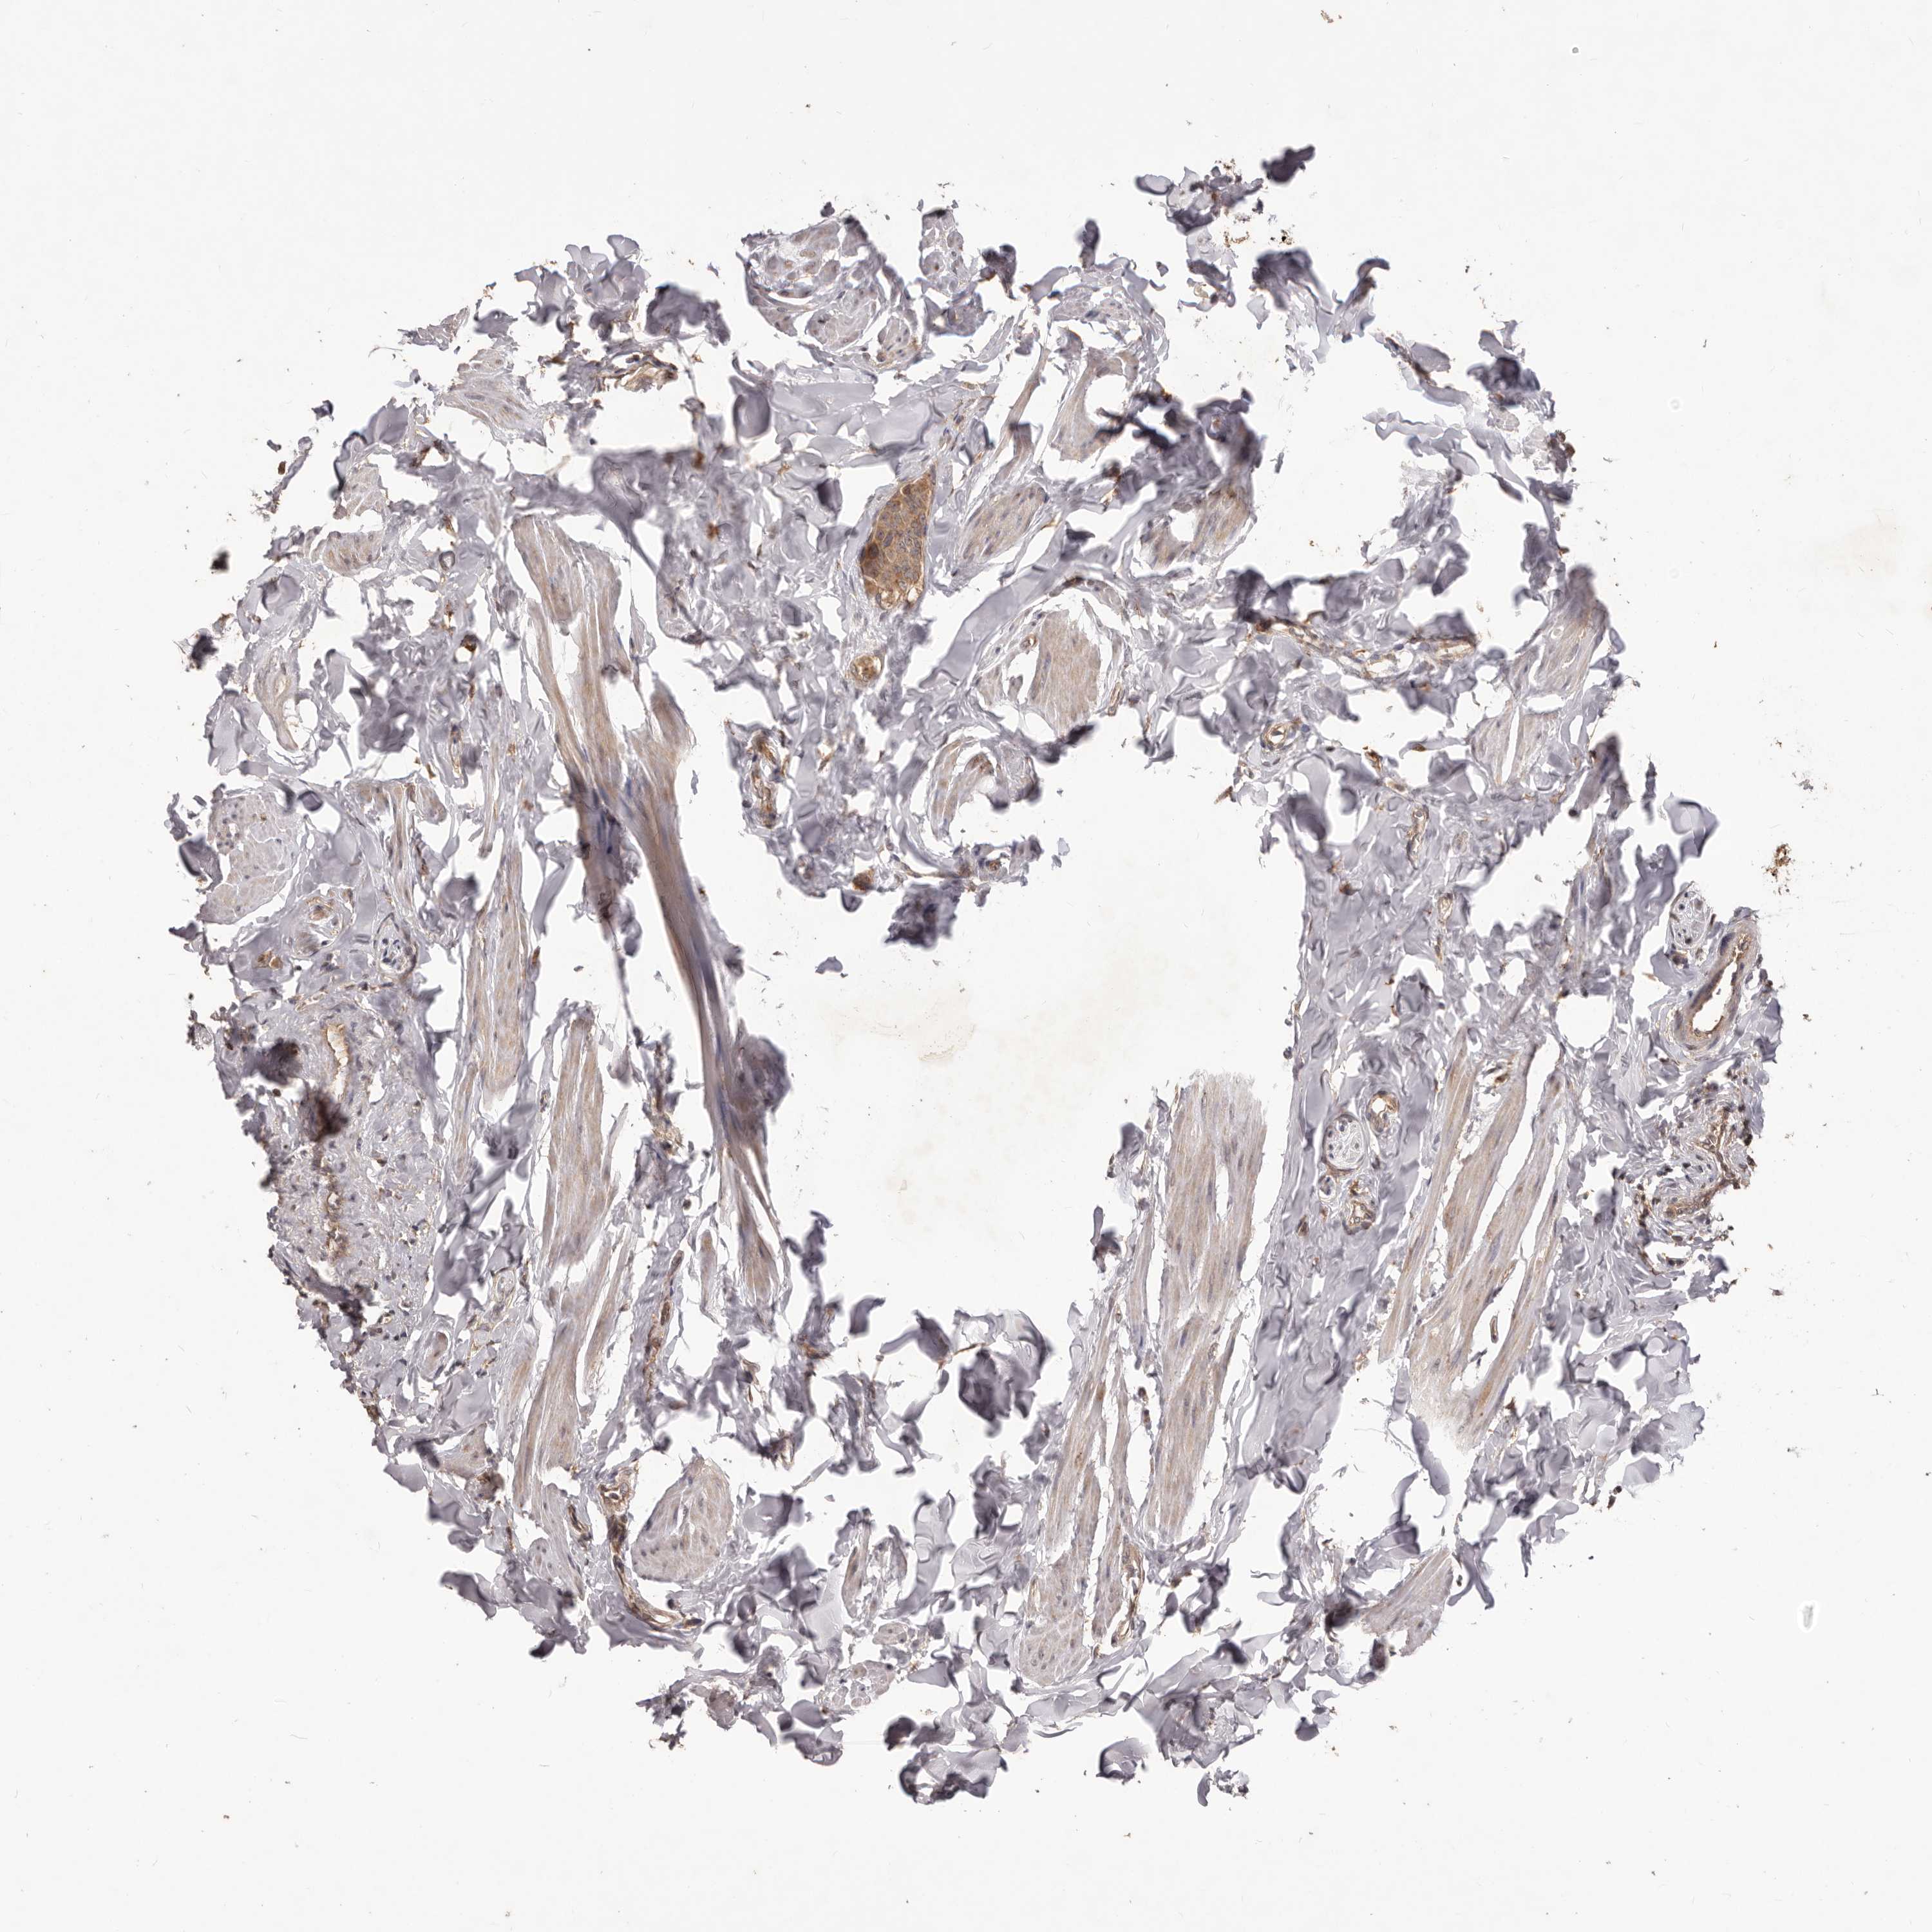

CANCER BREAST CANCER Show tissue menu

BRCA TCGA BRCA VALIDATION PROTEIN EXPRESSION